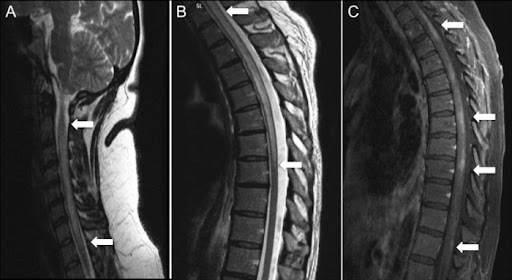

| Магнитно-резонансная томография (МРТ) спинного мозга | МРТ является ключевым методом диагностики. Она позволяет визуализировать очаги воспаления, отек и изменения структуры спинного мозга. Исследование проводится с контрастным усилением, что повышает его информативность и помогает выявить активное воспаление. Результаты МРТ обычно готовы достаточно быстро. |